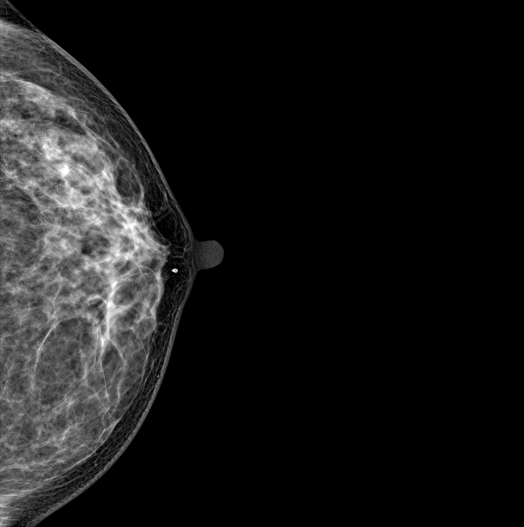

SYNTHESIZED 2D

HESTIA supports "Synthetic 2D" that generates 2D images only by tomography shooting without additional 2D shooting.